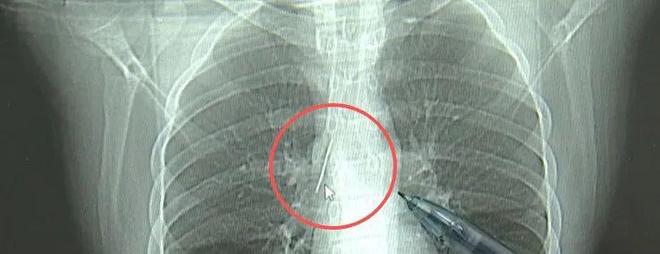

近日,安徽17岁小伙小陆参加征兵体检,胸片结果显示:胸腔内有一处金属高密度影,形态细长,像一根针。进一步的CT检查确认,异物是一枚金属针,斜插在肺组织内,位置十分凶险。

17岁小伙小陆参加征兵体检,发现胸腔内有根5cm缝衣针